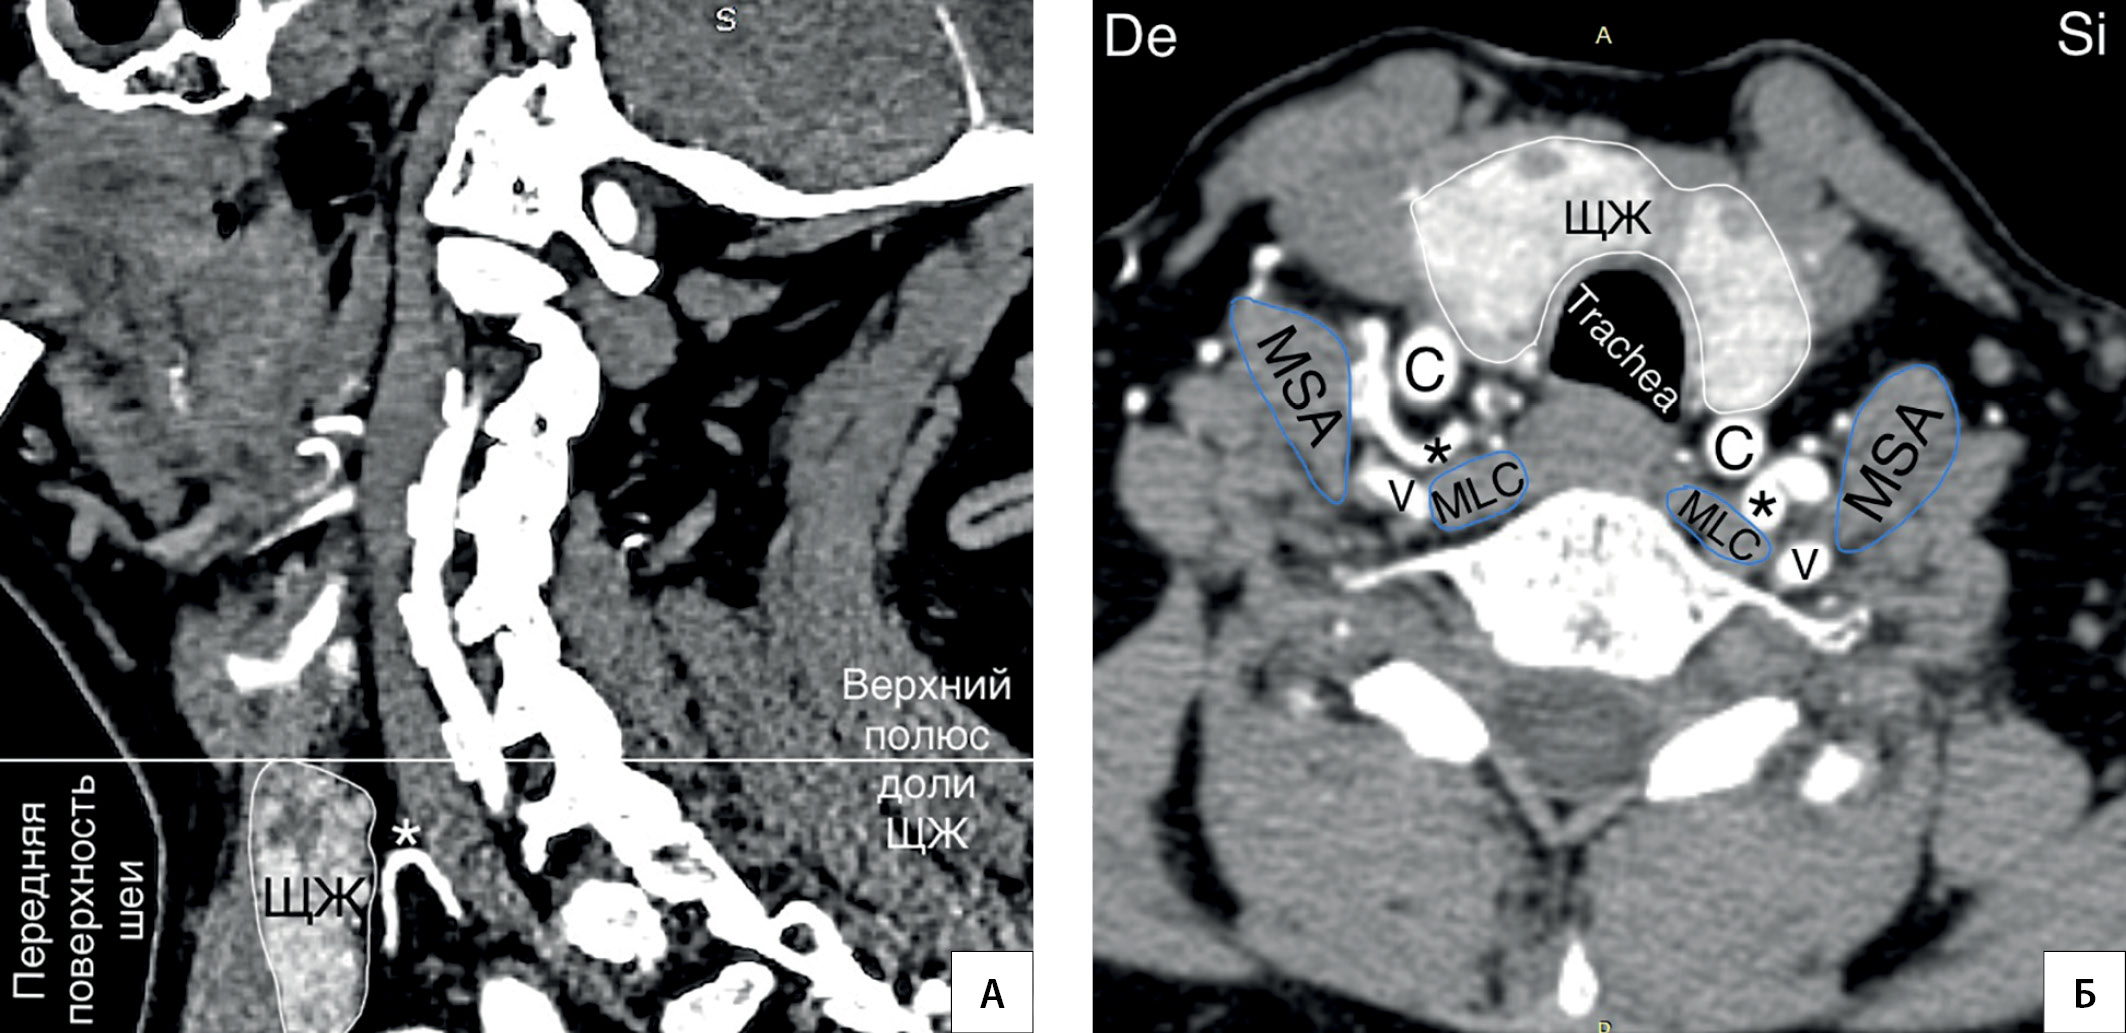

4. Рисунок 4. Колено НЩА располагается на уровне верхнего полюса доли ЩЖ. А — КТ-ангиограмма (фронтальный срез); Б — КТ-ангиограмма (горизонтальная плоскость); * — колено НЩА. C — a. carotis communis; V — a. vertebralis; MSA — musculus scalenus anterior; MLC — musculus longus colli; De — dextra; Si — sinistra. | |

|